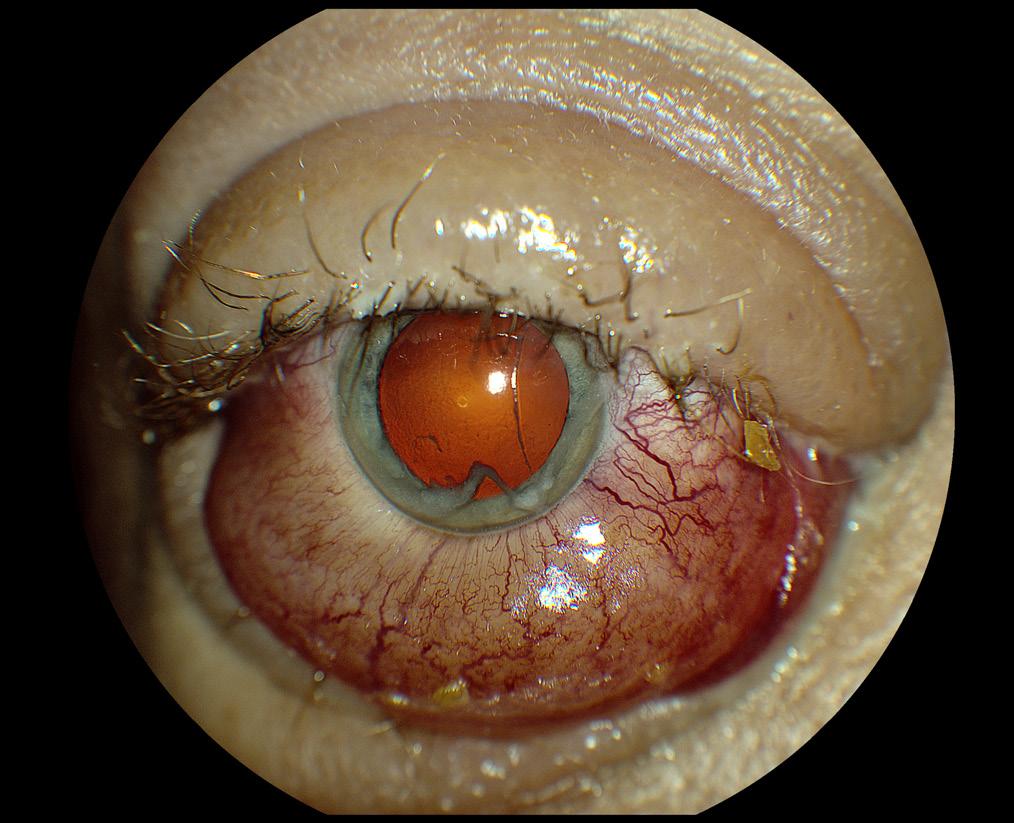

Case 3

Traumatic cataract in the right eye of a 3-year-old FS Siberian Husky mix breed dog.

The pet was adopted by the owners a few weeks prior to presentation. She had a history of injuries on both eyes, cause unknown, and was almost completely blind. The left eye showed such severe end-stage lesions that enucleation was recommended.

The right eye, which is represented in Figures 3 and 4, was still partially visual.

The eye shows minor conjunctival hyperemia. The pupil is pharmacologically dilated. The lens presents immature diffuse anterior and posterior cortical cataracts. A solid, roughly round dark foreign body is visible in a dorsal/central position within the lens (Figure 3). A radiograph of the dog’s head revealed multiple lesions from penetrated shotgun pellets. It was assumed that the small round foreign body within the right lens was indeed a birdshot and the cause of the cataract. Due to the absence of corneal scars, it was assumed that the pellet had penetrated the lens from the side and the back, perforating the sclera. The left eye had suffered much more severe injuries, and was not viable anymore. Lead is usually well tolerated within the eye, but unfortunately the trauma resulted in the presence of the cataract in the right eye. The owner elected cataract surgery and the removal of the foreign body for the right eye, and removal of the left eye. It was confirmed that the foreign body was indeed a lead pellet from a shotgun.

Figure 4 shows the same eye after extracapsular lens extraction surgery. Due to the damage present in the posterior lens capsule and anterior vitreous, caused by the trajectory of the pellet, it was elected not to insert an artificial intraocular lens (IOL). The corneal incision seen dorsally (few sutures) is larger than usual, as it was necessary for the removal of the pellet. The large capsulorexis is visible, as is the focal vitreal fibrotic strand. The dog was visual and comfortable after the procedure.

NIKON D3200, f/16, 1/200”, ISO-2200, 105mm focal length, 4 max aperture, auto flash.

Figure 3 Figure 4